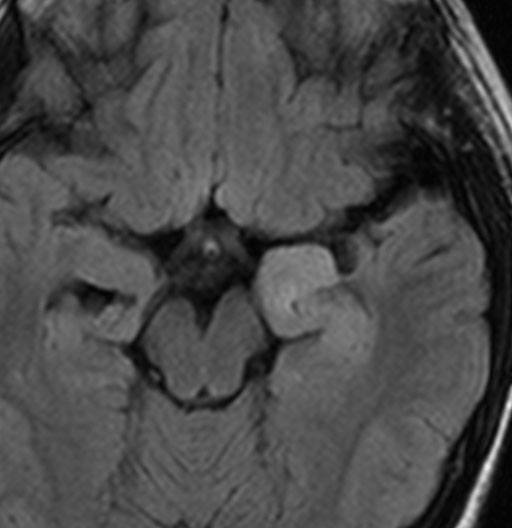

軽い右顔面神経麻痺で発症した小児で,右上下肢の軽度の失調症もありました。脳幹部(橋)の右背側から発生した腫瘍で,軽度の閉塞性水頭症を合併しています。左はT2強調画像で,橋の右側ににじむような浸潤像と浮腫があります。腫瘍は小嚢胞を形成してT2強調画像で実質は等信号です。真ん中の画像はCISS画像で橋が腫大しているのがよくわかります。右側はガドリニウム増強像で,全体が増強されてまだらな増強所見となっています。正中後頭下開頭で全摘出 gross total removal して,局所放射線治療とtemozolomide, cisplatine, etoposide, gleevec, hydoreaなどの化学療法を行いましたが,手術後4ヶ月で激しい播種再発を来しました。